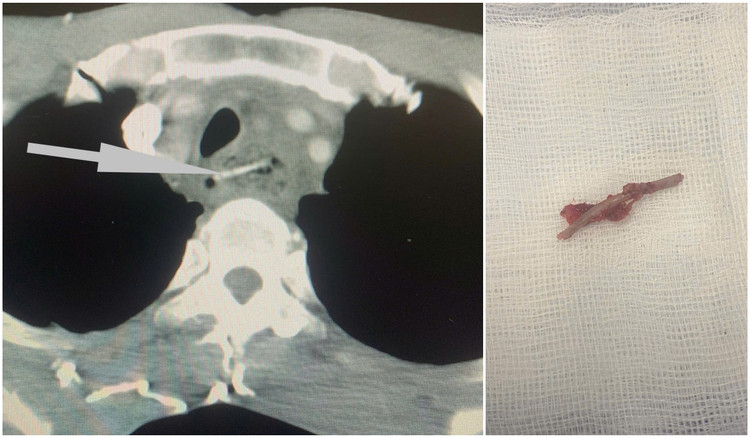

| Dị vật thực quản bệnh nhân H. gây áp xe thực quản - Ảnh BVCC |

Trường hợp đầu tiên là bệnh nhân Hà Văn H (63 tuổi), nhập viện ngày 5/2/2025 trong tình trạng nuốt đau, nuốt nghẹn ngày thứ 3. Các bác sĩ thăm khám, chụp cắt lớp chẩn đoán bệnh nhân H. bị hóc xương gà vùng thực quản gây áp xe thực quản. Bệnh nhân đã được nội soi lấy dị vật, sau đó mở thông dạ dày nuôi dưỡng để điều trị ổn định vùng thực quản bị áp xe.